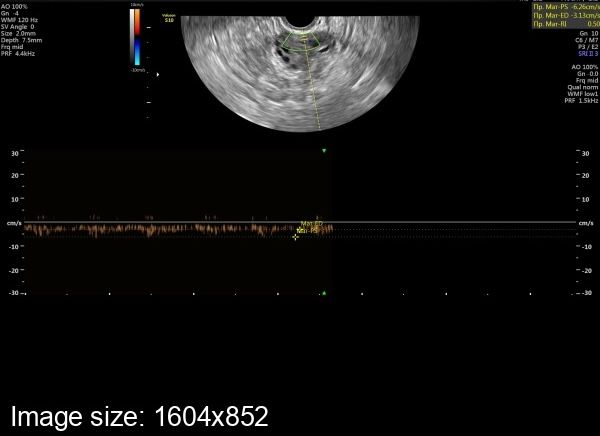

Объективно - по индексу резистентности.В сосудах нормального желтого тела снижение ИР в среднем до 0,44 происходит на 2 день после овуляции. И это значение не меняется в течение первых 5 дней второй фазы.

За неделю до месячных ИР повышаеся в среднем до 0,47 и затем постепенно увеличивается в среднем до 0,53 к концу менструального цикла.

Скорее всего, не было полноценной овуляции. Чтобы ответить точно сдаётся за неделю до месячных прогестерон и эстрадиол.